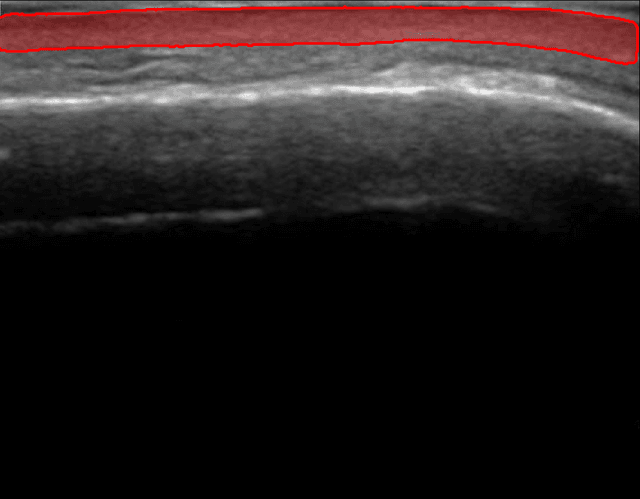

Nuestra IA segmenta instantáneamente tu capa dérmica. Obtén mediciones precisas de el grosor y el área de la dermis.